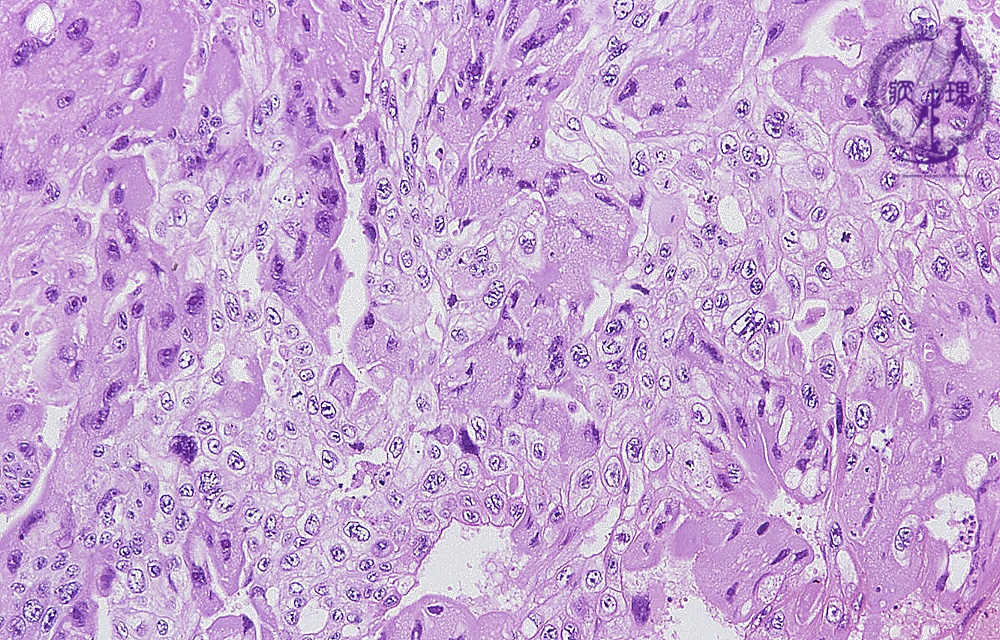

絨毛癌ミクロ像(HE弱拡大)

ミクロ像(HE弱拡大):好酸性で多核の合胞体栄養膜細胞(syncytiotrophoblast、黄色点線)に類似した腫瘍細胞と、淡明な細胞質を有する細胞性栄養膜細胞(cytotrophoblast、青色点線)に類似した腫瘍細胞のシート状増殖が認められる。前者の腫瘍細胞からはh-CGが産生・分泌される。